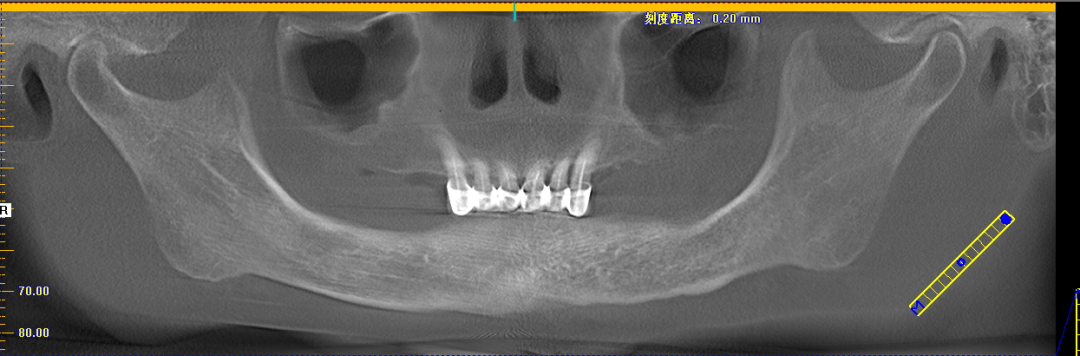

姚江武院长来为大家分享顾客术前牙片情况及种植方案。并现场讲解数字化全程导板种植技术与传统种植牙的区别和优势。

今天活动上有一位这样特殊的分享嘉宾——赖女士,今年69岁,需要种植的是下半口。赖女士为了想种好牙辗转了好几家医院,因为她的右边牙龈和舌头是连在一起的,去过其它医院说要割开才能种牙,后来打听到麦芽口腔姚院长临床经验丰富,过来看诊后,给出的主案可以用数字化导板进行种植牙,并不用割开原本连在一起的牙龈和舌头,赖女士听到此方案相当满意。